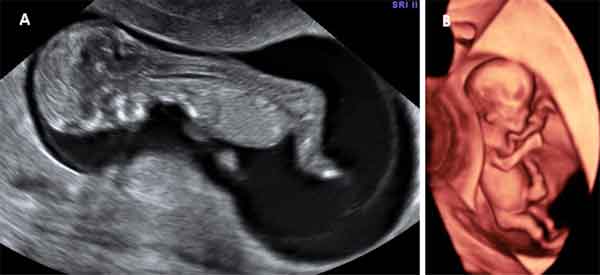

Al empezar la semana 11 de embarazo el bebé mide unos 45 milímetros pero ya pueden visualizarse órganos muy pequeños como los dedos de las manos o de los pies. La ecografía puede detectar las malformaciones fetales denominadas mayores (en extremidades, abdomen...).